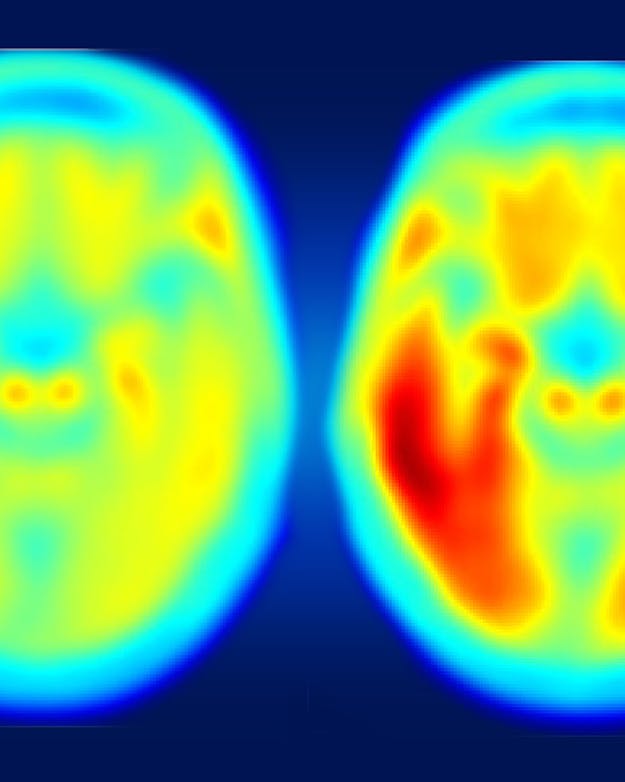

Hoe roder de kleur, hoe meer tau-eiwit in de hersenen. Links het gemiddelde brein van iemand die cognitief gezond is, waar ook wat tau is opgehoopt. In mensen met milde symptomen van de ziekte van Alzheimer (rechts) is er veel meer samenklontering van tau. Er is een verband tussen de hoeveelheid tau en de ernst van cognitieve problemen.